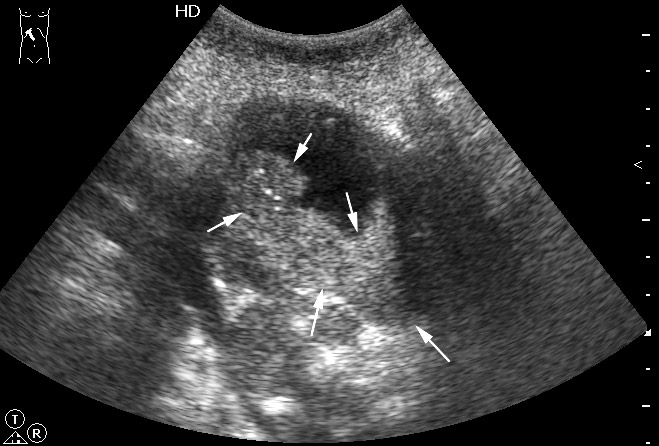

Рак желчного пузыря #2

Женщина - пенсионерка. Жалобы скудные, дискомфорт в правом подреберье.